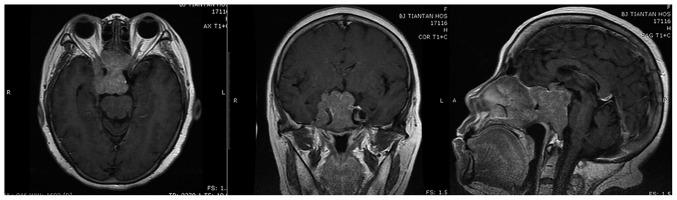

Pituitary null cell adenoma is a challenging clinical condition, and its pathogenesis remains to be elucidated. We performed this study to determine the roles of C5orf66-AS1, NORAD, and TINCR in the pathogenesis and invasion of pituitary null cell adenomas. Expression of the three long non-coding RNAs in pituitary null cell adenoma tissues of 11 patients and normal pituitary tissues from four donors was examined by performing quantitative reverse transcription-polymerase chain reaction. We found that C5orf66-AS1 expression was lower in pituitary null cell adenoma tissues than in normal pituitary tissues. Moreover, C5orf66-AS1 expression level was significantly lower in invasive pituitary null cell adenomas than in non-invasive ones. After transfection of C5orf66-AS1 into pituitary adenoma cells, assessment of cell viability and invasion suggested that overexpressed C5orf66-AS1 inhibited cell viability and cell invasion. In silico algorithms predicted several cis- and trans-acting target genes of C5orf66-AS1, including PITX1 and SCGB3A1. In addition, expression of some of the predicted target genes was determined using microarray data of another cohort with pituitary null cell adenomas. It showed that some of these target genes were differentially expressed between pituitary null cell adenoma tissues and normal pituitary tissues as well as between invasive and non-invasive tumors. Co-expression analysis in RNA sequencing data showed that PAQR7 was the most correlated gene of C5orf66-AS1 and that several predicted trans-acting target genes, including SCGB3A1, were highly correlated with C5orf66-AS1. NORAD and TINCR expression was not statistically significant in the complete cohort; however, a negative correlation was observed between NORAD expression and maximum tumor diameter in some subgroups. These results indicate that C5orf66-AS1 suppresses the development and invasion of pituitary null cell adenomas. However, our results do not provide enough statistical evidence to support the roles of NORAD and TINCR in the development and invasion of pituitary null cell adenomas.